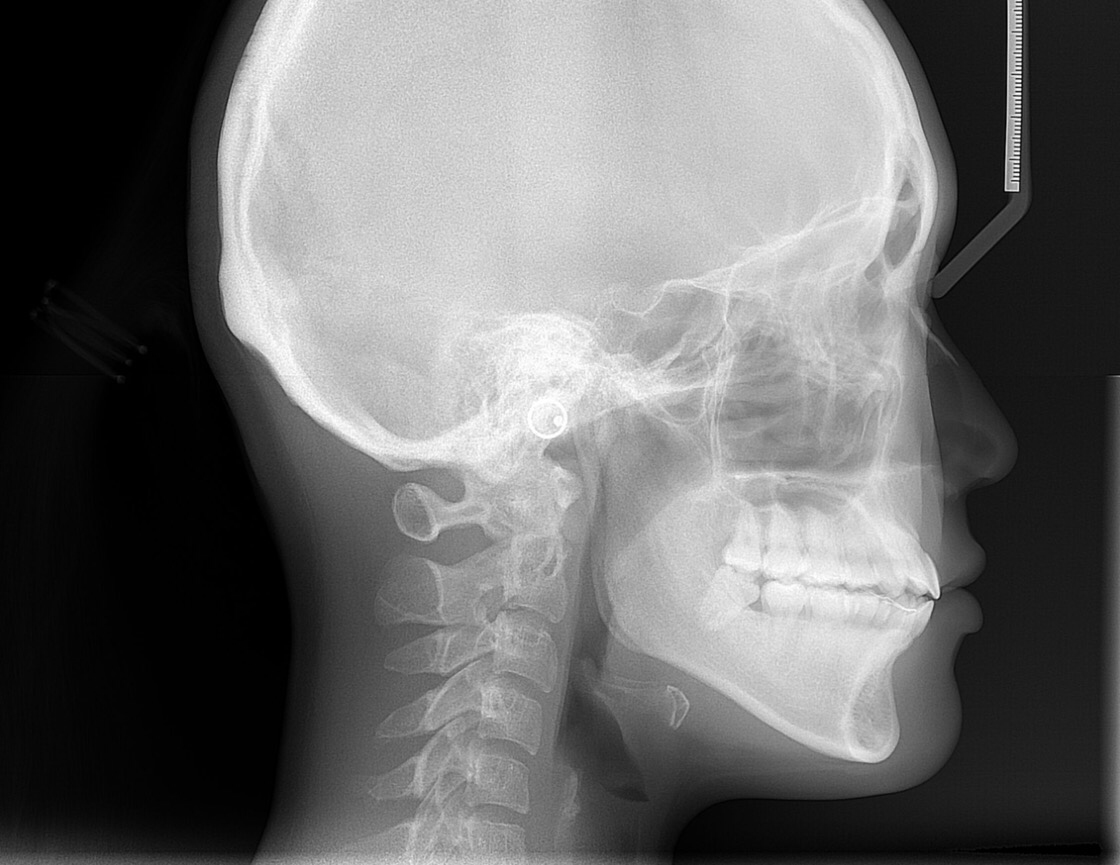

Panorex & Ceph Digital X-Rays

Digital X-rays provide several advanced imaging options designed to save time, provide clearer dental photos, and expose patients to less radiation than traditional X-ray technology.